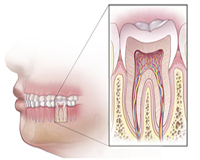

To understand a root canal procedure, it helps to know about the anatomy of the tooth. Inside the tooth, under the white enamel and a hard layer called the dentin, is a soft tissue called the pulp. The pulp contains blood vessels, nerves and connective tissue, and helps to grow the root of your tooth during development. In a fully developed tooth, the tooth can survive without the pulp because the tooth continues to be nourished by the tissues surrounding it.

CROWN : This is the part of the tooth you can see above the gumline. ROOT : This part of the tooth sits in the bone below the gum. The root of your tooth is usually twice as long as the crown, the part you see above the gumline.